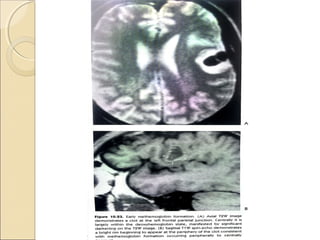

Gradient EchoGradient Echo

Pros:

fast technique

Cons:

 More sensitive to magnetic susceptibility

artifacts

 Clinical use:

eg. Hemorrhage , calcification